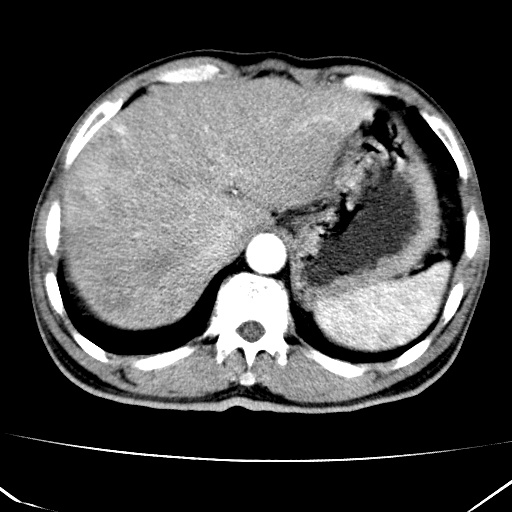

标题: CT17975:请求会诊。男、57岁。上腹部胀痛2天。临床诊断:糜 [打印本页]

标题: CT17975:请求会诊。男、57岁。上腹部胀痛2天。临床诊断:糜

肝脏多发类圆形低密度影,考虑肝脏转移瘤,肝胃韧带一淋巴结肿大,原发?胃癌?

考虑胃癌并肝脏及腹膜后淋巴结转移;不排除淋巴瘤。

肝内转移瘤,腹腔及腹膜后淋巴结转移。